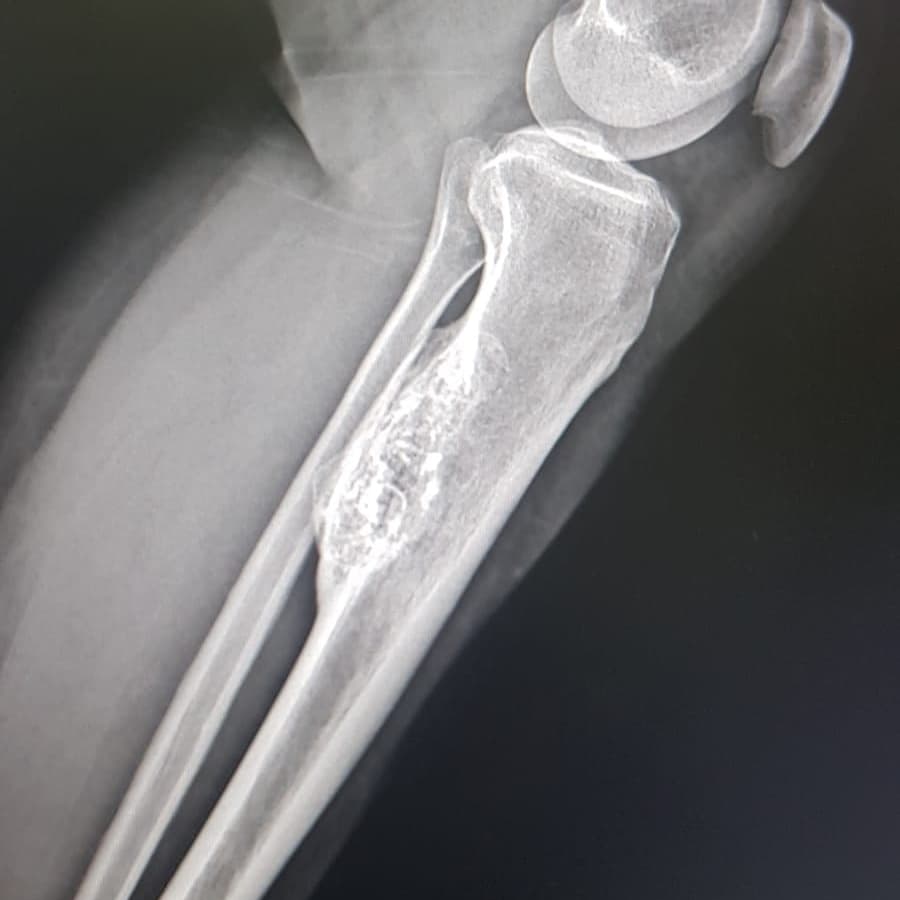

📝Diz ağrısıyla gelen 49 yaşındaki hasta 📝Ayırıcı tanı için ileri tetkik önerilir. #radyoloji #tıbbigörüntüleme

📝Diz ağrısıyla gelen 49 yaşındaki hasta

📝Ayırıcı tanı için ileri tetkik önerilir.